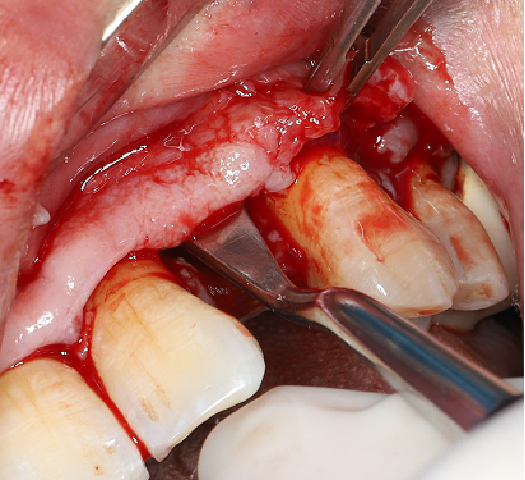

使用12#镰形刀片沿21、22、23做龈沟内切口,于24近中做垂直附加切口。

翻开全厚粘骨膜瓣,暴露22颊侧牙槽骨,微创拔除22。

搔刮22拔牙创,暴露22牙槽骨表面,开放骨髓腔。

采用不切开骨膜的软组织扩张术——Soft Tissue Extend释放软组织张力

记录翻瓣后原始软组织瓣长度,使用软组织搔刮器(Soft Tissue Extender)冠根向搔刮软组织瓣。

在不切断骨膜的前提下,使用软组织刮治器反复搔刮软组织瓣,可以起到延长软组织瓣的作用。

使用软组织搔刮扩张前后对比:可见在不切断骨膜的前提下,使用软组织搔刮即可获得软组织瓣延长8-9mm。